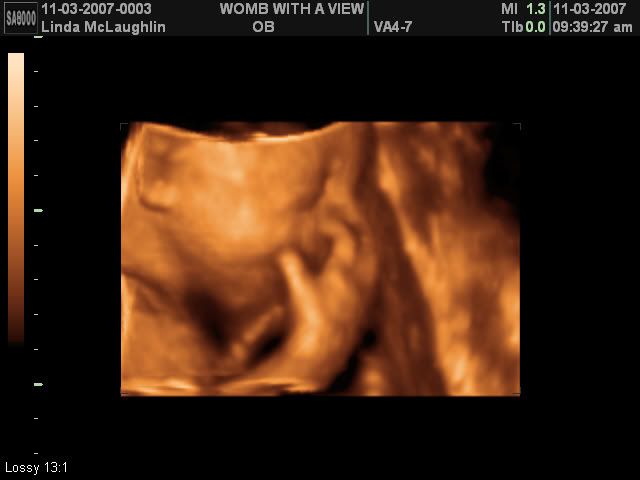

I guess the first thing to start off with is my surprise for M&M a few weeks ago. I got them a 3-d ultrasound session! It was so much fun! We have confirmed she is 100% girl :-) Unfortunately, Miss Baby M wanted nothing to do with picture taking that day so the ultrasound tech had to keep jiggling my belly to get her to turn around - haha!

Anyway, here's a few pictures of M&M's beautiful baby girl <3